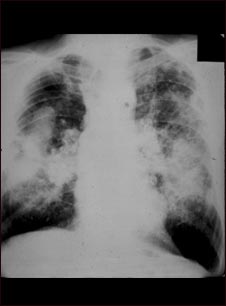

Neumoconiosis en trabajadores del carbón; complicada #2

Esta imagen muestra la neumoconiosis complicada del minero. En la parte superior y media de ambos pulmones, hay áreas difusas, masivas y claras que corren paralelas y están superpuestas a un fondo de pequeñas áreas claras, difusas y difíciles de distinguir, que cubren ambos pulmones. Las enfermedades que pueden explicar estos hallazgos en una radiografía son la neumoconiosis complicada del minero (NCM), silicotuberculosis, y cáncer metastásico de pulmón.